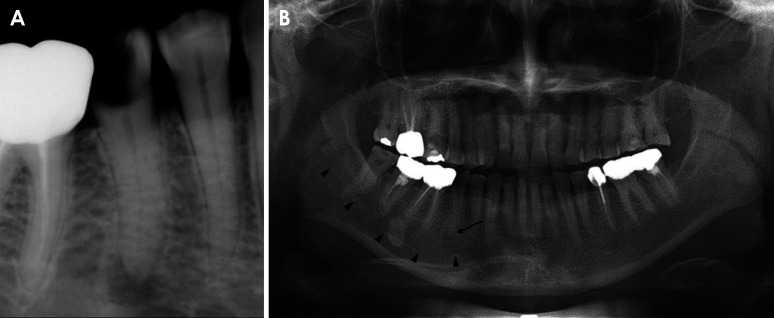

Components derived from an infected lesion within the bone can spread through various passages in the mandible, particularly via the mental foramen. Radiologically, the spread of infection is typically nonspecific and challenging to characterize; however, multislice computed tomography (MSCT) can effectively detect pathological changes in soft tissues and the bone marrow space. This report describes the case of a 55-year-old woman who experienced mental nerve paresthesia due to a periapical infection of the right mandibular second premolar. MSCT imaging revealed increased attenuation around the periapical lesion extending into the mandibular canal and loss of the juxtamental foraminal fat pad. Following endodontic treatment of the tooth suspected to be the source of the infection, the patient's symptoms resolved, and the previous MSCT imaging findings were no longer present. Increased bone marrow attenuation and obliteration of the fat plane in the buccal aspect of the mental foramen may serve as radiologic indicators of inflammation spreading from the bone marrow space.